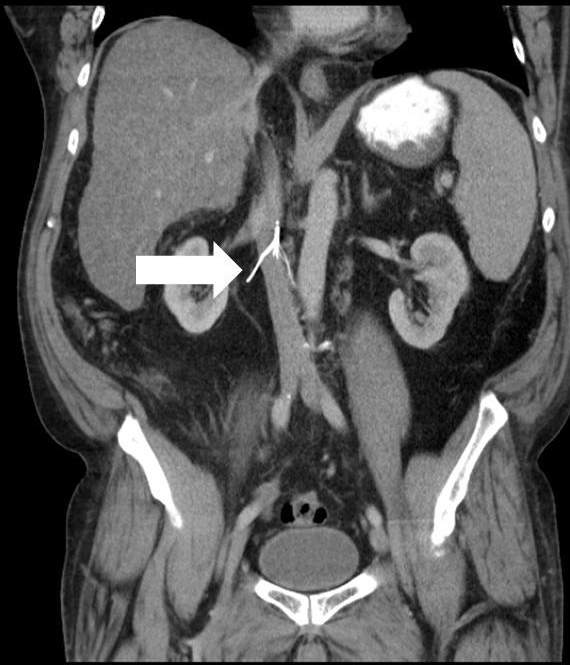

neoplastic obstruction

IVC flow obstruction caused by primary tumors that typically propagate from hepatic or renal veins

extrinsic tumors can also cause compression or invasion into IVC (abdo tumors along midline)

sono feats:

visualization of intraluminal tumor

tumor will demonstrate blood flow within, thrombus wont

visualization of extrinsic tumor mass that compresses & obstructs IVC

variable echogenicity

dilation of IVC and tributary veins below lvl of obstruction

continuous flow below the point of obstruction

Which of the following matches with the findings below?

neoplastic IVC obstruction